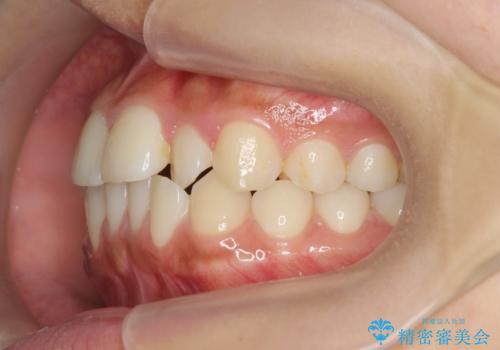

- 前歯のガタつき、上下たがい違いになっている歯並び(クロスバイト)の改善を求めて来院されました。

インビザラインによる矯正治療を行いますが、クロスバイトの改善をワイヤー部分矯正で事前に行うことにより治療期間の短縮する治療計画を立案します。

上下すれ違った噛み合わせはマウスピースでは改善に時間がかかり、またねじれが残ってしまうことも多々見られます。

マウスピース矯正を行う前に、これらの症状の改善の得意なワイヤー部分矯正を行うことで治療期間を短縮し、確実にすれ違いを改善することができます。